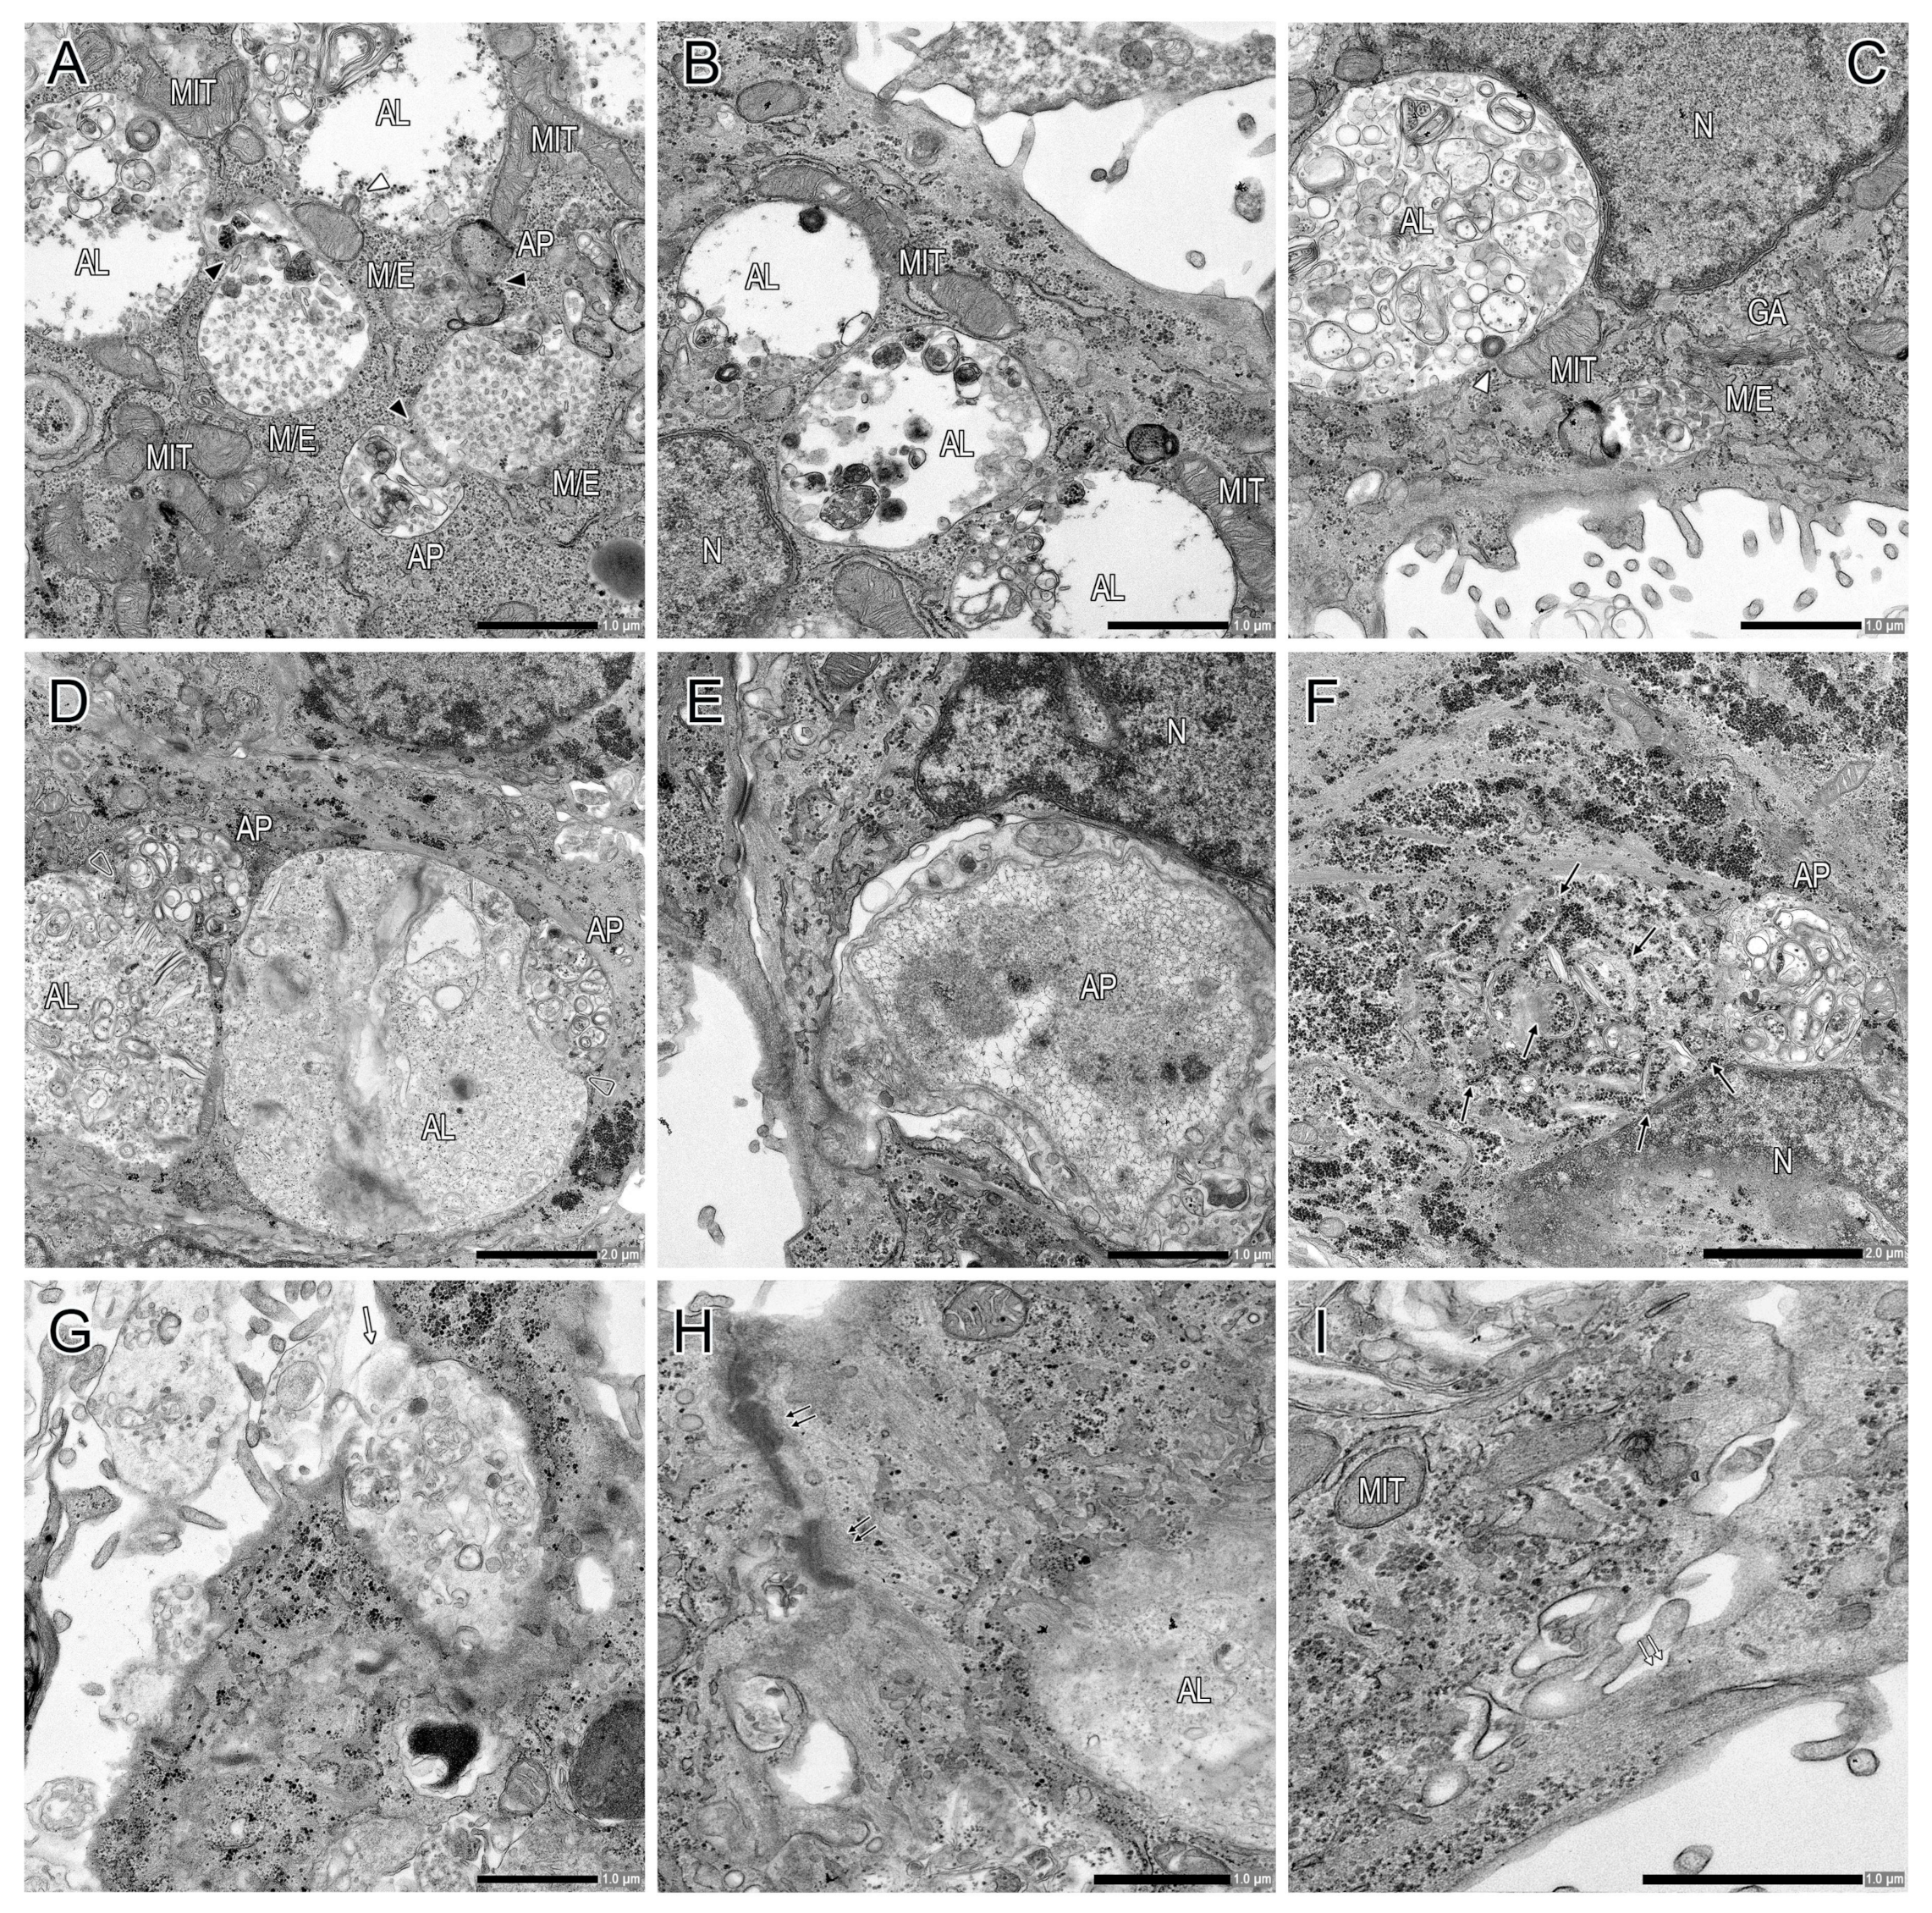

2.2. Transmission Electron Microscopy Analysis of Cultured Primary CTB Cells